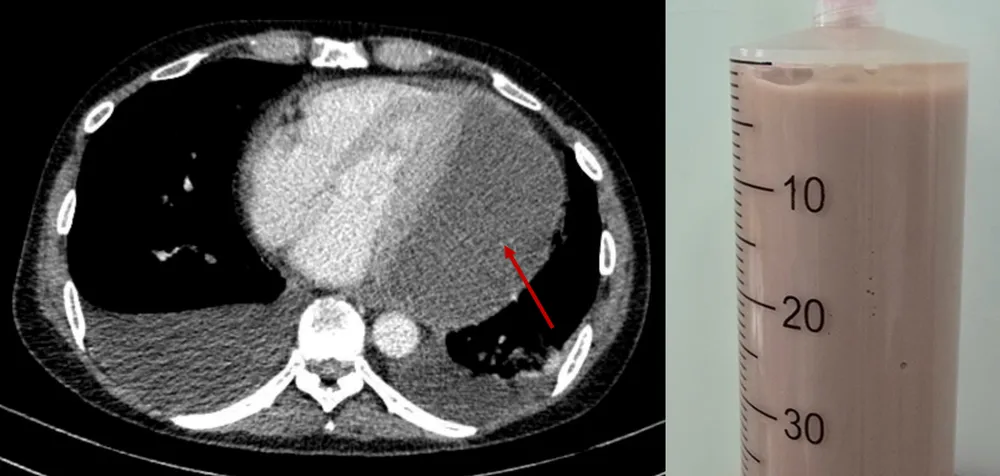

Hình chụp CT lồng ngực xác chẩn với mũi tên đỏ thể hiện lớp dịch mủ chèn ép tim và dịch mủ đặc rút ra được qua chọc dịch màng ngoài tim

Trước tình hình nguy cấp, chuyên gia từ các chuyên khoa nội tim mạch, phẫu thuật tim, chẩn đoán hình ảnh, hô hấp, nội tiêu hóa thảo luận và quyết định can thiệp chọc hút dịch mủ ra khỏi màng ngoài tim khẩn cấp. “Đây là một ca chọc hút không đơn giản và tiềm ẩn nhiều nguy cơ do khối mủ nằm ở vị trí khó tiếp cận, dịch đặc quánh. Tuy nhiên, nhờ kinh nghiệm chuyên môn và sự hỗ trợ của thiết bị siêu âm hiện đại tại giường bệnh, các bác sĩ đã hút thành công 500ml mủ đặc, giảm nhanh áp lực lên tim”, BS-CK2 Dương Văn Mười Một thông tin.